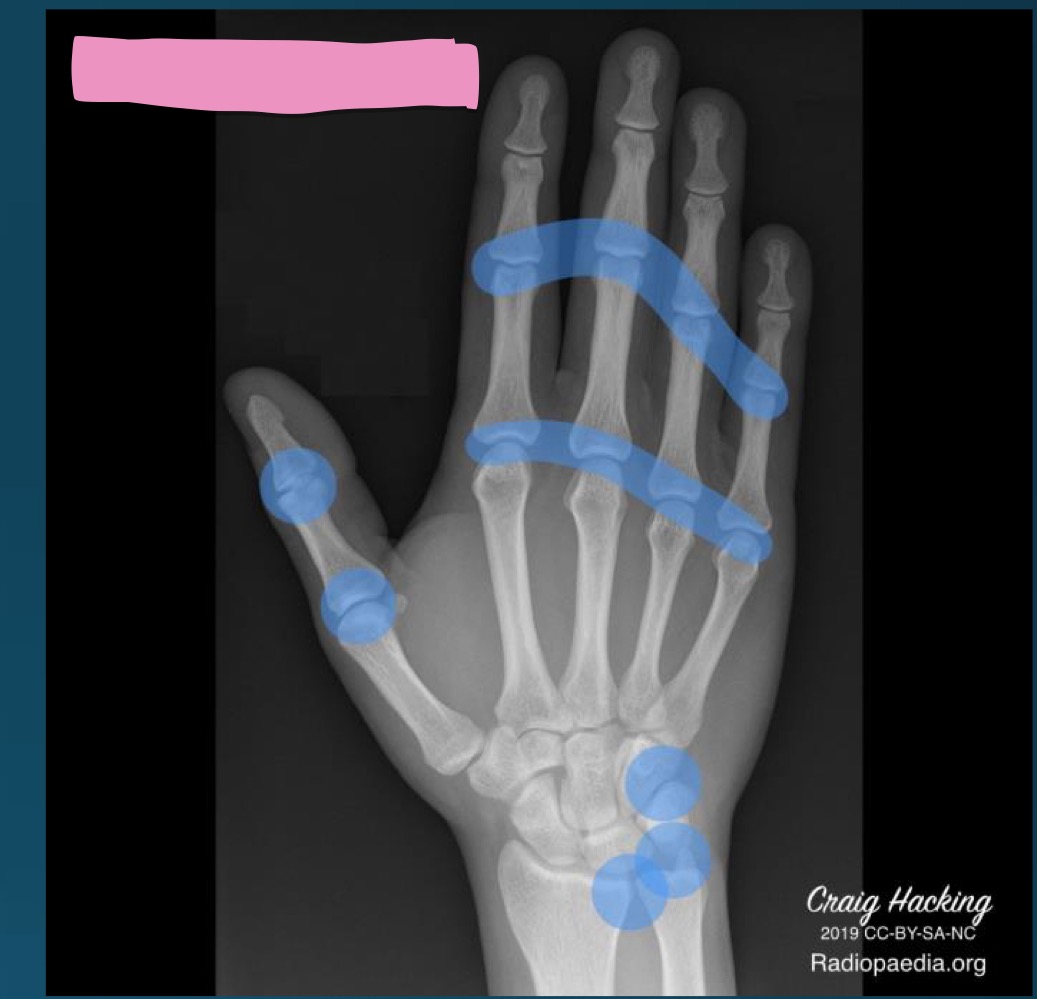

what are hallmark radiographic signs of RA

bilateral symmetic involvment

periarticular soft tissue swelling

marginal erosions

uniform loss of joint space

juxta articular osteoporosis

ADI instability

what is the diagnosis

RA